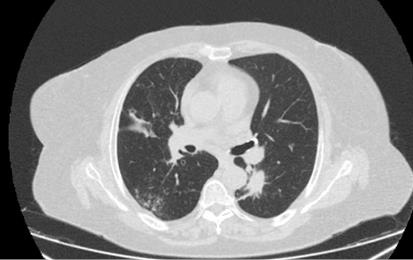

Por mejoría del cuadro clínico, se programó TC de tórax control al mes en la que se visualizaron dos imágenes nodulares a nivel de lóbulo superior derecho. (Figura 2) La punción percutánea con aguja fina de la lesión consolidativa nodular concluyó en la ausencia de atipias en la anatomía patológica, pero con marcadores tumorales TTF1, CK 7 y P63 positivos. Una nueva TC de tórax mostró franca mejoría de las imágenes nodulares previamente descritas, pero con la aparición de un nódulo de 15 mm en lóbulo inferior izquierdo. (Figura 3) Posteriormente, se decidió realizar biopsia quirúrgica por medio de una videotoracoscopía (VATS) de la lesión de la base pulmonar izquierda y la anatomía patológica informó un patrón inflamatorio inespecífico (ver exámenes complementarios).

Nódulo de 15 mm en lóbulo inferior izquierdo.